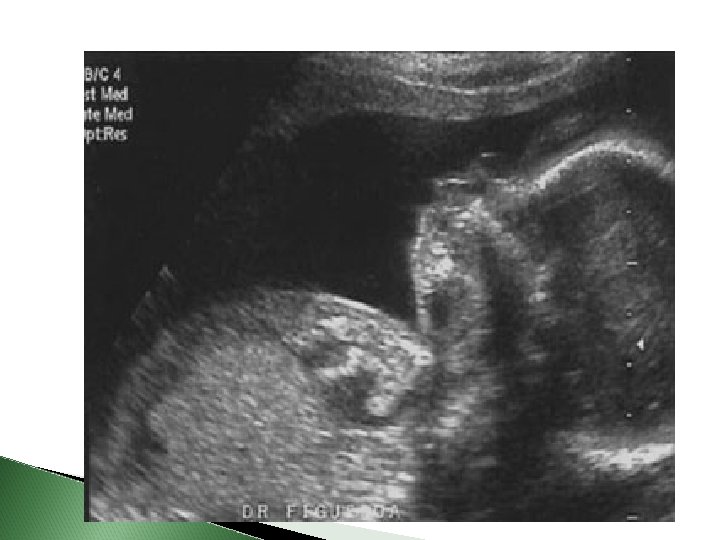

� Acúmulo de fluido no tecido subcutâneo. � Sinal ultrassonográfico: aumento da espessura da pele > 5 mm (edema subcutâneo), associado a um ou mais derrames serosos (espaço pleural, cavidade peritoneal ou pericárdio). � Placenta pode se encontrar espessada e edemaciada